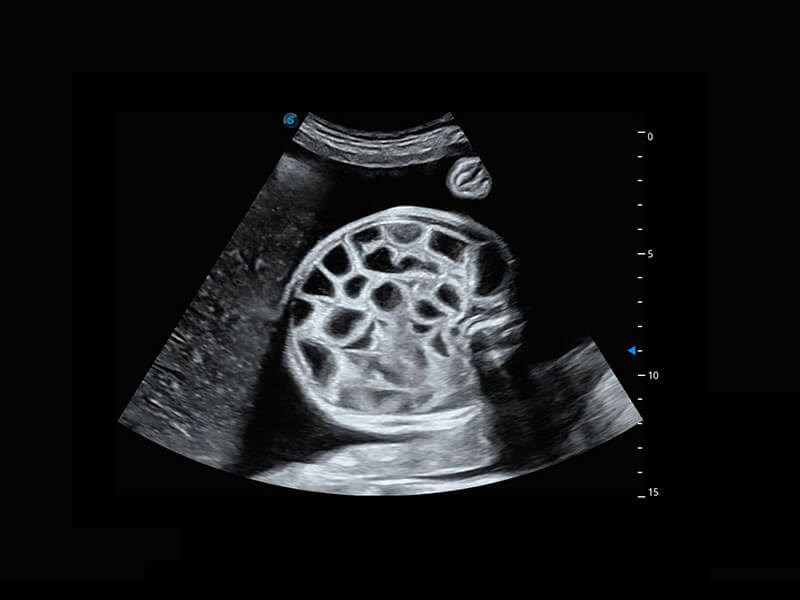

P60搭载一系列胎儿心脏成像技术,实现精细的胎儿心脏评估。

右室双出口

胎心容积成像